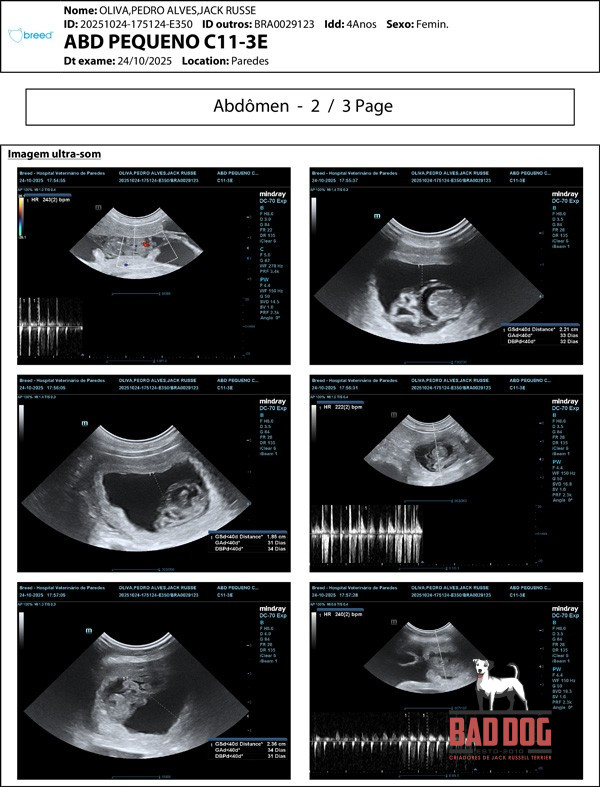

Ninhada PHI 2

Phi 2 - PROMO PHI2_oliva-rx